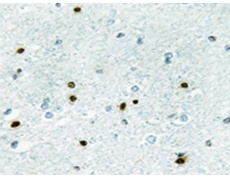

IHC positive control: |

Human brain tissue |

IHC Recommend dilution: |

50-100 |